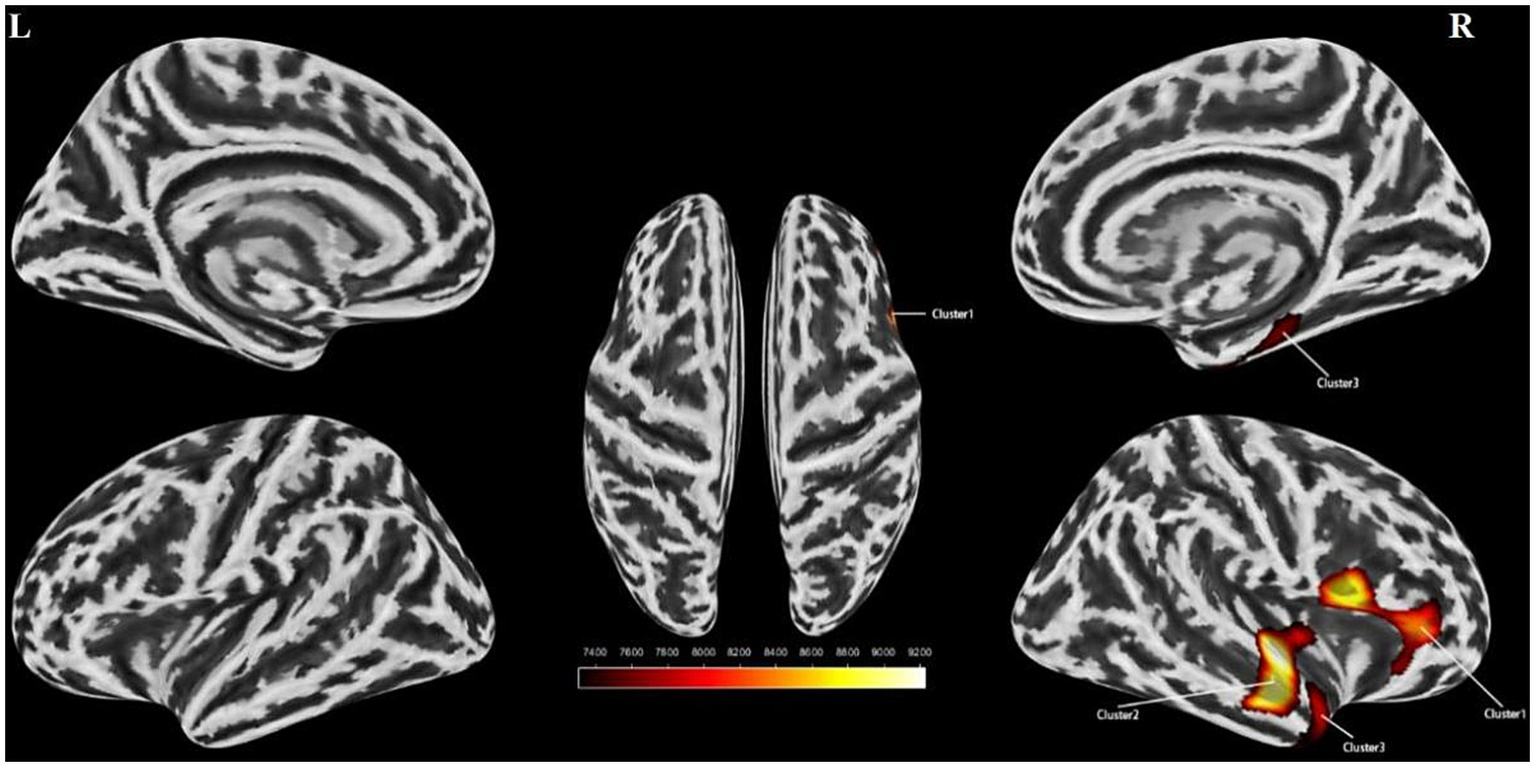

Data results based on SBM analysis

An independent t-test was conducted to assess cortical thickness, sulcus depth, fractal dimension, and cortical fold characteristics of the stuttering group versus the control group. Multiple corrections were applied to compare the statistical outcomes. Our findings indicated a substantial decrease in cortical folds specifically in the right insula and the right superior temporal gyrus among individuals with stuttering (Table 3 and Figure 2). However, no significant disparities were observed between the two groups in terms of cortical surface area, sulcus depth, or fractal dimension. Furthermore, a partial correlation analysis was performed between cortical fold metrics and stuttering severity scores among the stuttering group. These results revealed no significant correlation between the three brain regions and stuttering severity scores (P > 0.05).

Figure 2

Surface based morphometry-based analysis of the brain regions where the two groups differed significantly in cortical folds. Clusters with reduced cortical folds in the stuttering group compared to the control group (yellow clusters) Cluster 1 represents the right insula, Cluster 2 represents the right superior temporal gyrus, and Cluster 3 represents the right superior temporal gyrus. l, left hemisphere; r, right hemisphere. Color bands indicate t-values (red indicates that cortical folds were smaller in the stuttering group than in the healthy control group). SBM, Surface-based Morphometry.